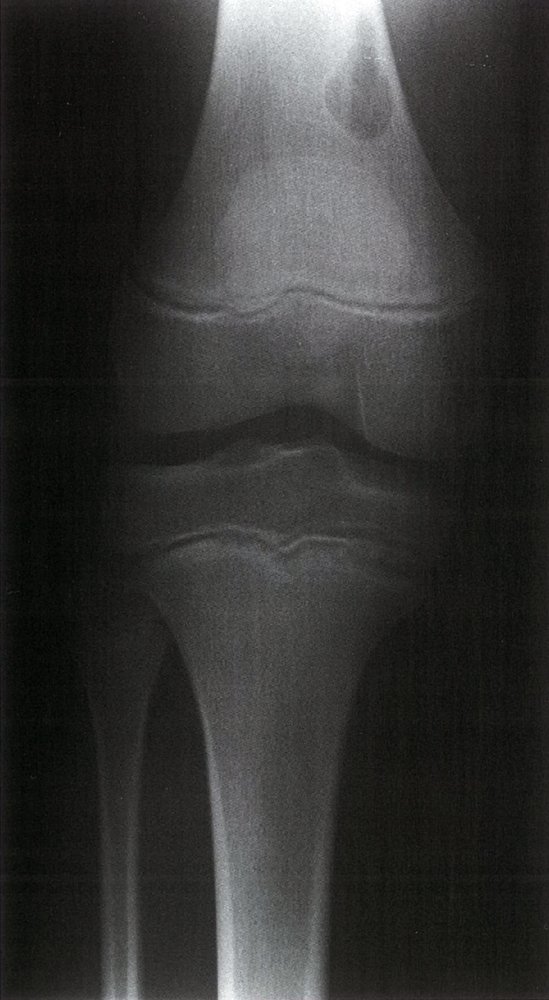

• Description: benign but locally aggressive tumor composed of giant cells that arise from the bone marrow [1]

• Epidemiology: peak incidence between 20 and 40 years

• Clinical features

• Found in the epiphysis or metaphysis of long bones (especially knee region)

• Pathological fractures

• Local pain and swelling

• Limited range of motion

• Diagnostics

• X-ray: multicystic osteolytic lesions (soap-bubble appearance)

• Histopathology

• Mononuclear, RANKL-expressing cells (neoplastic)

• Multinucleated giant cells (are reactive and resemble osteoclasts)

• Treatment: curettage and bone grafting or en-bloc resection to minimize recurrence rate

• Prognosis: risk of malignant degeneration increases with age; may spread to the lungs